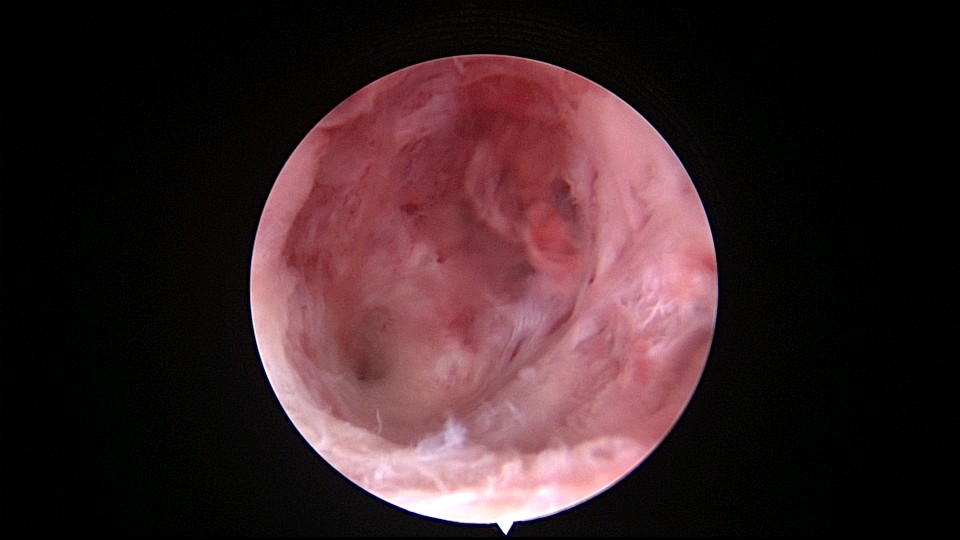

患者56岁,G2P1,剖宫产1次。安环30年,绝经7年,外院取环失败,形成假道。子宫后倾后屈位,宫颈外口萎缩狭小,宫颈管扩张膨大,宫颈管左前壁假道,宫颈内口狭窄坚硬,宫腔镜见宫腔偏向右后方,并向左后侧屈,镜子艰难进入宫腔,O型环位置正常,异物钳取出,宫腔无其他异常。